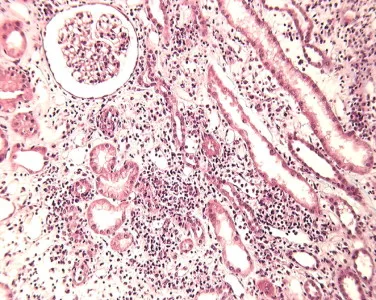

Injúria Renal Aguda (revisão Lancet 2025)

Injúria Renal Aguda (revisão Lancet 2025)